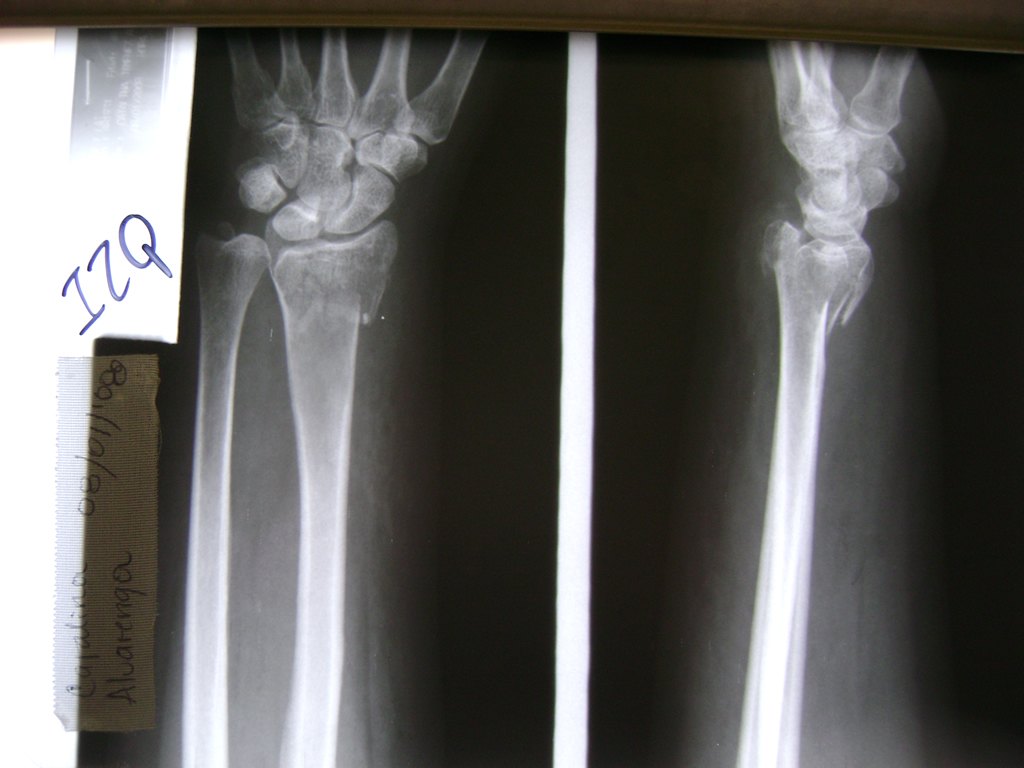

Cirugías de Calcaneo - Cirugías de Muñecas y Manos

Los procedimientos más comunes en cirugía de la mano son aquellos destinados a reparar traumatismos, incluyendo lesiones de tendones, nervios, vasos sanguíneos, y articulaciones; huesos fracturados; y quemaduras, cortes, y otros daños de la piel.